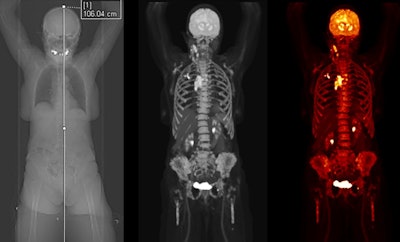

Siemens Healthineers has received clearance from the U.S. Food and Drug Administration for Biograph Vision Quadra, a new PET/CT scanner with a large 106-cm axial field of view.

Initially launched at the 2020 European Association of Nuclear Medicine (EANM) meeting, Biograph Vision Quadra is able to perform simultaneous whole-body imaging from the top of the head to the thigh. The system's 106-cm axial field of view is four times that of Siemens' Biograph Vision 600 scanner.

The new system is designed for clinical use as well as translational research, such as creating therapies and new clinical procedures. Siemens is also highlighting the scanner's 3.2-mm silicon photomultiplier (SiPM) detector technology and time of flight (ToF) performance, which enable more anatomical coverage of a patient in one bed position than a standard PET/CT scanner, according to Siemens.